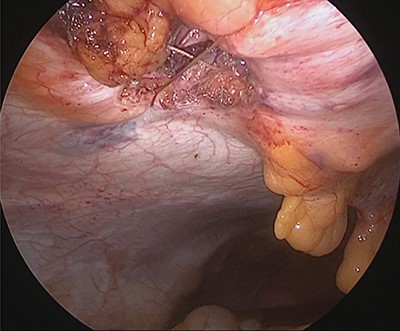

Under general anesthesia, with the patient in the lithotomy position, a 5-mm trocar was inserted into the lower right abdomen using the optical method. Observation of the abdominal cavity revealed a hernia orifice with a diameter of ~1 cm at the upper aspect of the umbilicus (Fig. 3). Two additional 5-mm trocars were inserted into the left side of the abdomen. The hernia sac was significant scarring. We then made an incision around the hernia orifice using a hook-type electrocautery electrode to expose the muscle layer (Fig. 4). The hernia sac was pushed from the surface of the body using a pean, inverted into the abdominal cavity, and excised as much as possible using electrocautery (Fig. 5). At that point, we employed the VersaOne™ Fascial Closure System to close the fascia and peritoneum at the port site.